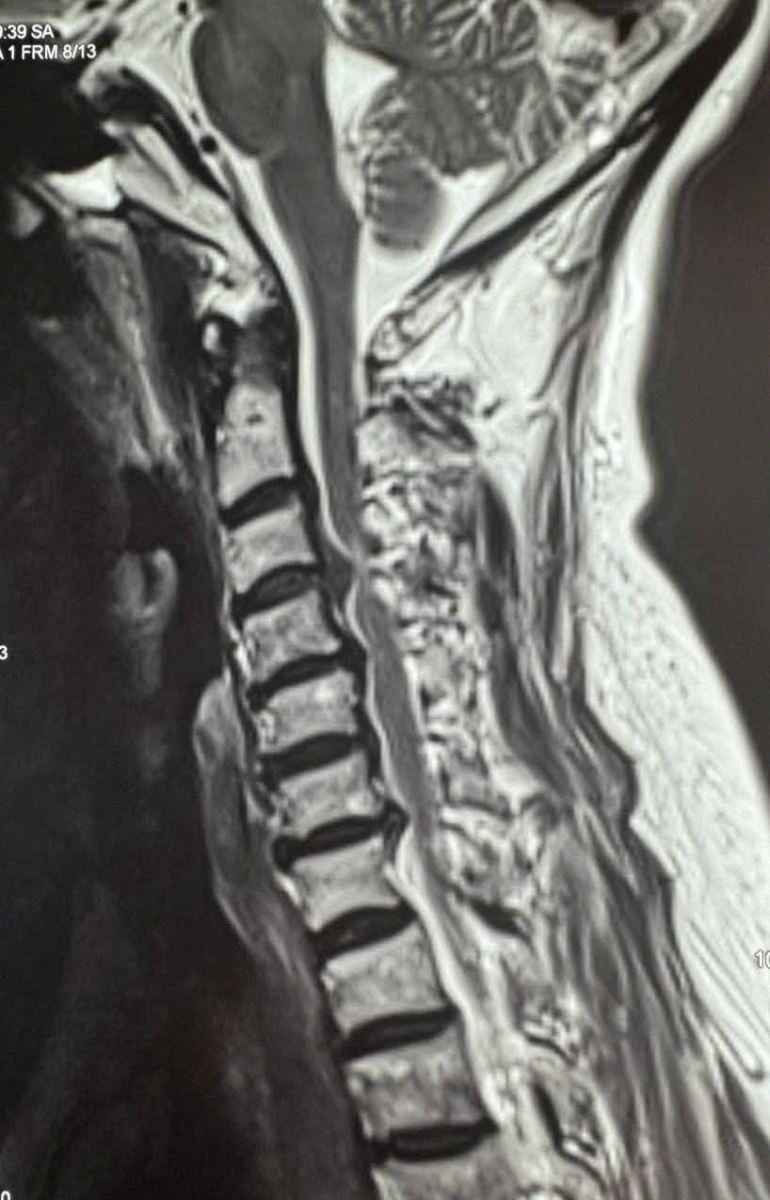

Qua thăm khám và chụp X-quang, MRI cột sống cổ, các bác sĩ xác định bệnh nhân bị thoát vị đĩa đệm C3–C4 thể trung tâm lệch trái, kèm phù tủy cổ, có nguy cơ tổn thương thần kinh tiến triển.

Bệnh nhân được phẫu thuật ACDF C3–C4 (lấy nhân đĩa đệm thoát vị, giải phóng chèn ép tủy – rễ thần kinh, hàn xương và cố định cột sống cổ lối trước).